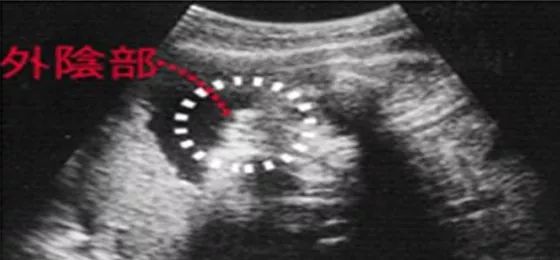

女宝宝四维彩超图

三条白线是明显的女宝特征,如果没有看到明显的三条白线,就看两腿之间有没有突出的东东,且中间有小凹槽的,就是女宝